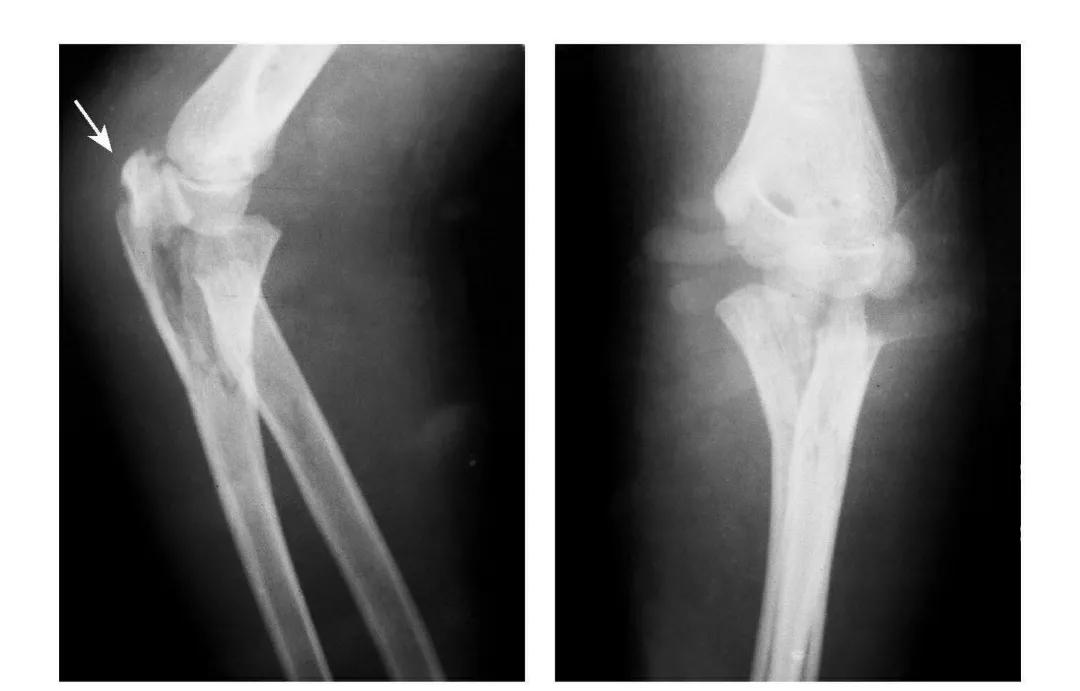

肘过伸应力综合征

例:①鹰嘴突劈裂骨折;②肱骨小头及滑车基底部骨折且整体前移;③肱骨内上髁Ⅱ型骨折;④肱骨外髁Ⅱ型骨折。